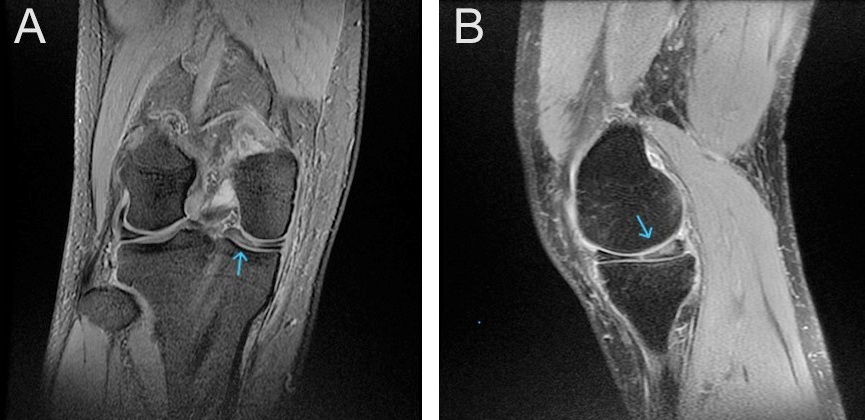

Magnetic resonance imaging (MRI) of the right knee demonstrates a medial discoid meniscus with increased thickness and abnormal morphology. A horizontal tear is identified, characterized by a linear hyperintense signal extending parallel to the tibial plateau. In addition, a complex tear involves the posterior horn, with irregular signal changes extending to the articular surface on T2-weighted images (Fig. 2).

Figure 2: Coronal (a) and sagittal (b) T2-weighted magnetic resonance imaging of the right knee showing a discoid medial meniscus with complex posterior horn tear (arrow).